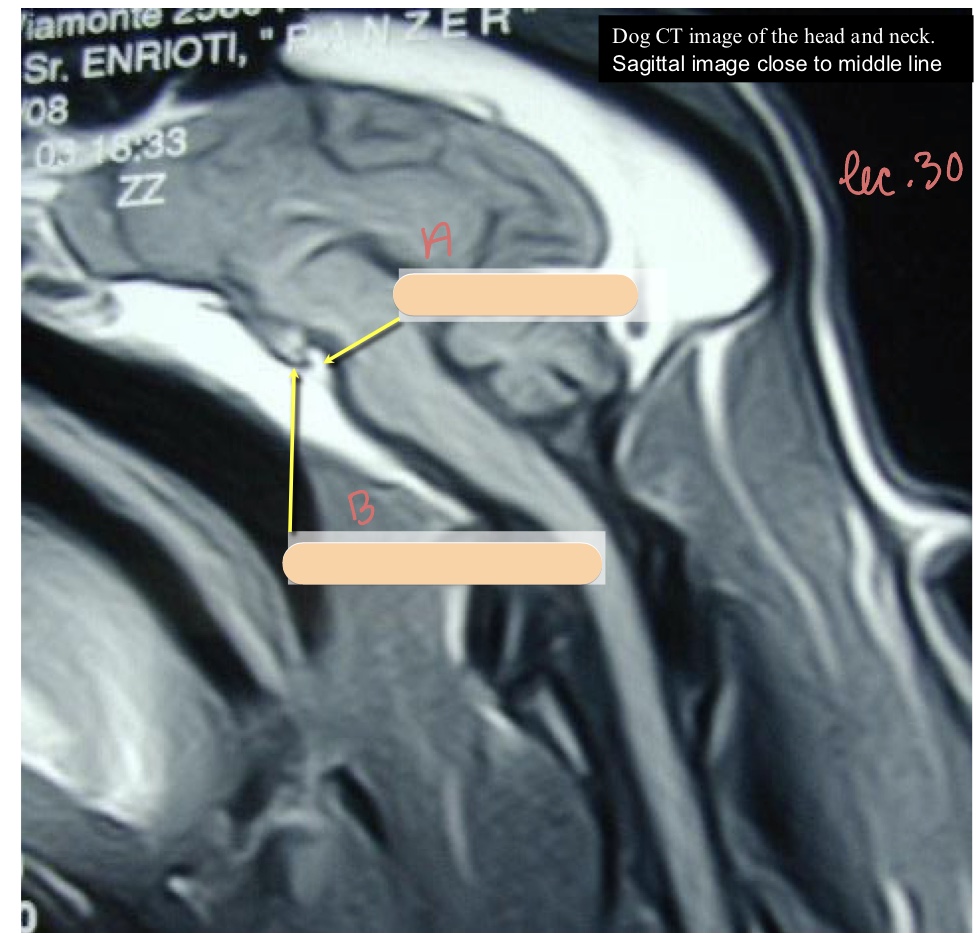

The hypophyseal fossa houses what structure? In what depression is it located?

hypophysis (pituitary gland)

sella turcica

What is the name of the caudal-most bony prominence of the sella turcica?

dorsum sellae